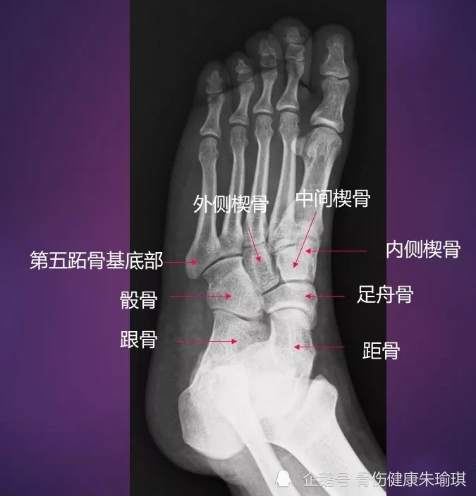

足部x线解剖(足正位片)

学习《x线读片指南》骨,关节系统——足

足部的x光图像